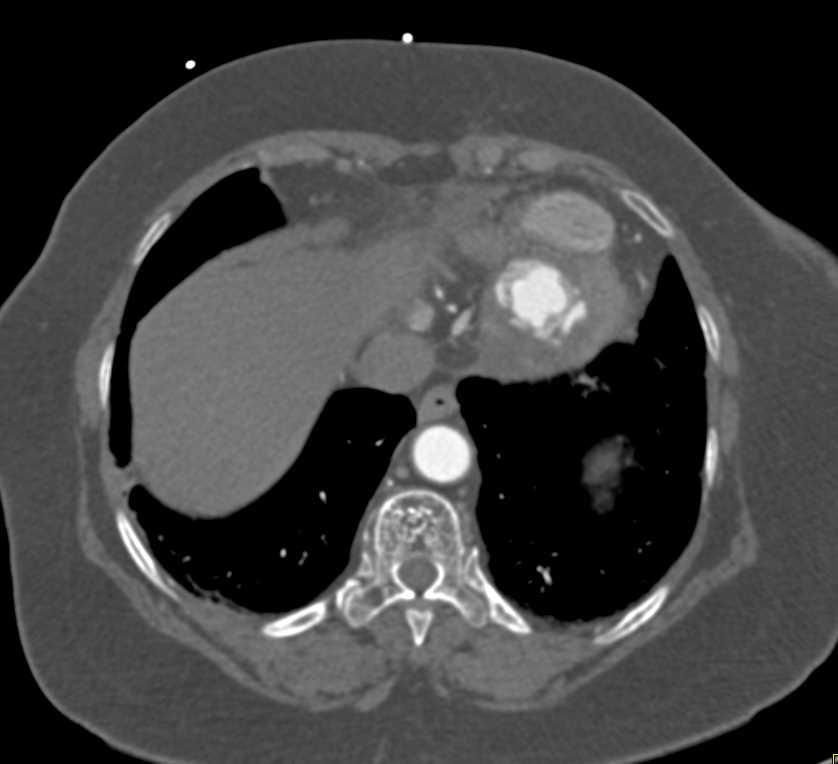

Left Ventricular Aneurysm